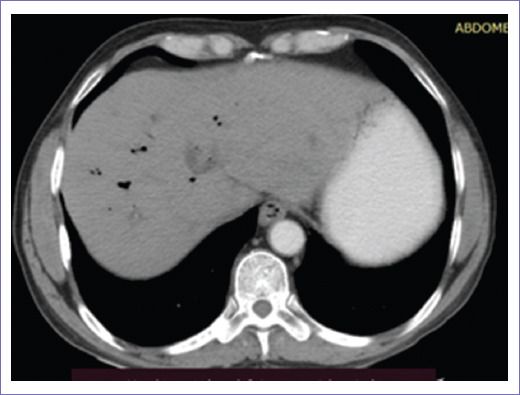

La tomografía abdominopélvica simple y contrastada de abril de 2022 reportó vía biliar intrahepática con presencia de gas en su interior de manera generalizada, colédoco con diámetro de 12 mm, prótesis que se extiende hasta conducto pancreático y segunda porción de duodeno, en la porción final se delimitaba engrosamiento focal de 15 mm, vesícula sin litos en su interior, con neumobilia (Figs. 3 y 4).